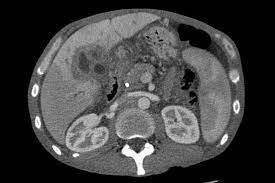

Liver Cancer Symptoms In Child : Https Encrypted Tbn0 Gstatic Com Images Q Tbn And9gctu Fqmi1tkivdxowm7rrvjaxigls8q Ro3qz8ucstxyu3e0cf7 Usqp Cau : These changes are the result of the interaction between a person's genetic factors and three categories of.. There are two main types of liver tumours in children: Although the symptoms may be related to another liver disorder or some other ailment, it's best not to let them go undiagnosed. They are produced in the body: Liver cancer symptoms and diagnosis. Liver cancer presents a special challenge because you may not notice any symptoms when the disease is starting and in its early stages.

Hepatoblastoma and hepatocellular carcinoma (hcc). Signs & symptoms of childhood cancer. Hepatoblastoma diagnosis starts with discussing with your child's symptoms and medical history with his or her pediatric liver cancer treatments depend on the type (hepatoblastoma or hepatocellular carcinoma) and stage of your child's disease, as well as your. Liver cancer is rare in children and adolescents. Every 3 months until the child is 4 years old, an abdominal ultrasound exam is.

Learn about the two main forms of pediatric liver cancer signs and symptoms of liver cancer may depend on the size of the tumor and if it has spread outside the liver.

Symptoms are more common after the tumor becomes large. In children, the cause of meningitis is mainly enteroviruses, penetrating into the body through food, water, dirty objects. Liver cancer symptoms often do not appear in the early stages. Liver cancer is rare in children and adolescents. Therefore, any child should be seen by a gp or other healthcare professional if you are concerned. Symptoms of childhood liver cancer vary from child to child. Although the symptoms may be related to another liver disorder or some other ailment, it's best not to let them go undiagnosed. These fatty acids will be taken to the liver for gluconeogenesis to elevate the. Signs and symptoms of childhood liver cancer include a lump or pain in the abdomen. The liver is one of the largest organs in the body. Infections that should be excluded: Every 3 months until the child is 4 years old, an abdominal ultrasound exam is. Liver cancer usually has no initial symptoms or may have vague symptoms such as fatigue, fever, chills, and night sweats.

Liver cancer in both children and adults is sometimes called a silent disease. this is because there are generally no early liver cancer symptoms.